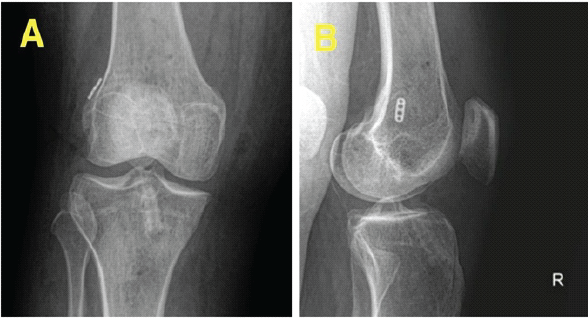

Graft fixation was achieved on the femoral side using a cortical button and on the proximal tibia using an interference screw. The reconstructed ACL was then reinforced by a lateral extra-articular tenodesis (LET) to provide rotational stability. Post-operative radiograph shows normal positioning of the ACL and LET tunnels (Fig. 7a and b).

Figure 7: (a and b) Post-operative radiographs.